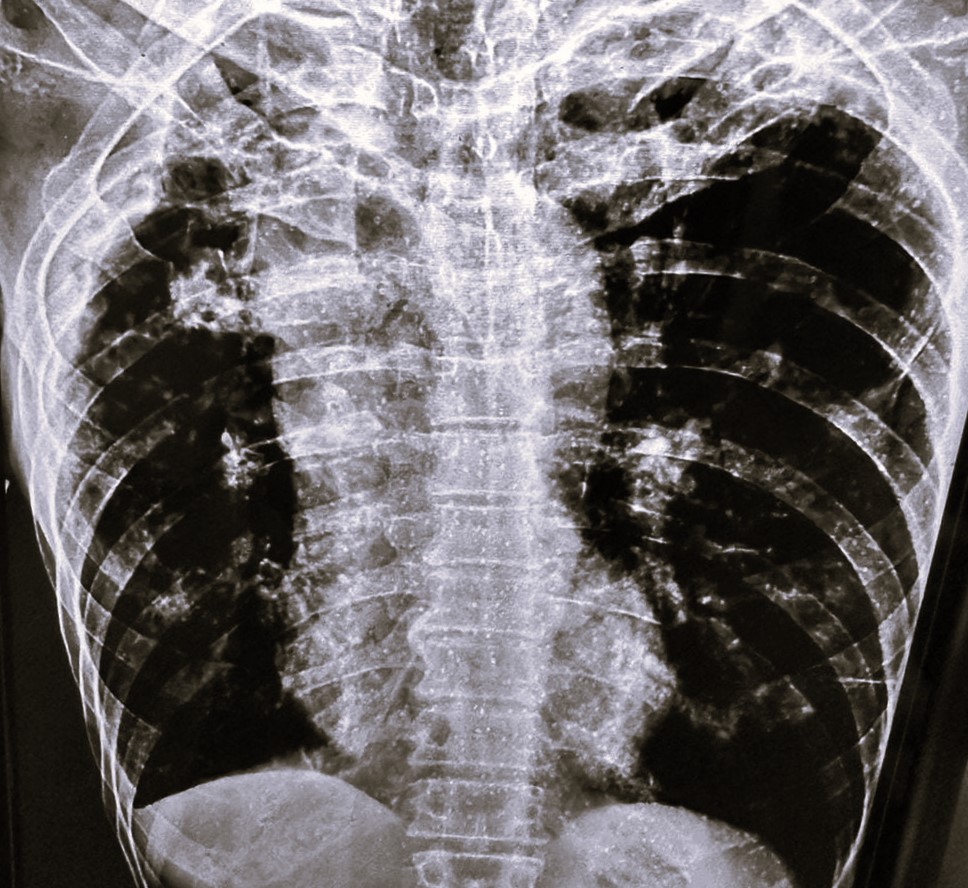

| 338 | IGGMC, Nagpur, Nagpur | P2 | 29-4134 | Rupesh Dongse | Consent taken on Paper | 43 Yrs. |

Provisional Diag : Consolidation

Final Diag : Bilateral Consolidation Community Acquired Pneumonia With Type 1 Respi Failure In Cronic Alcoholic |

Non-TB Case (Confirmed) | Bilateral Consolidation | Abnormality visible on x-ray |